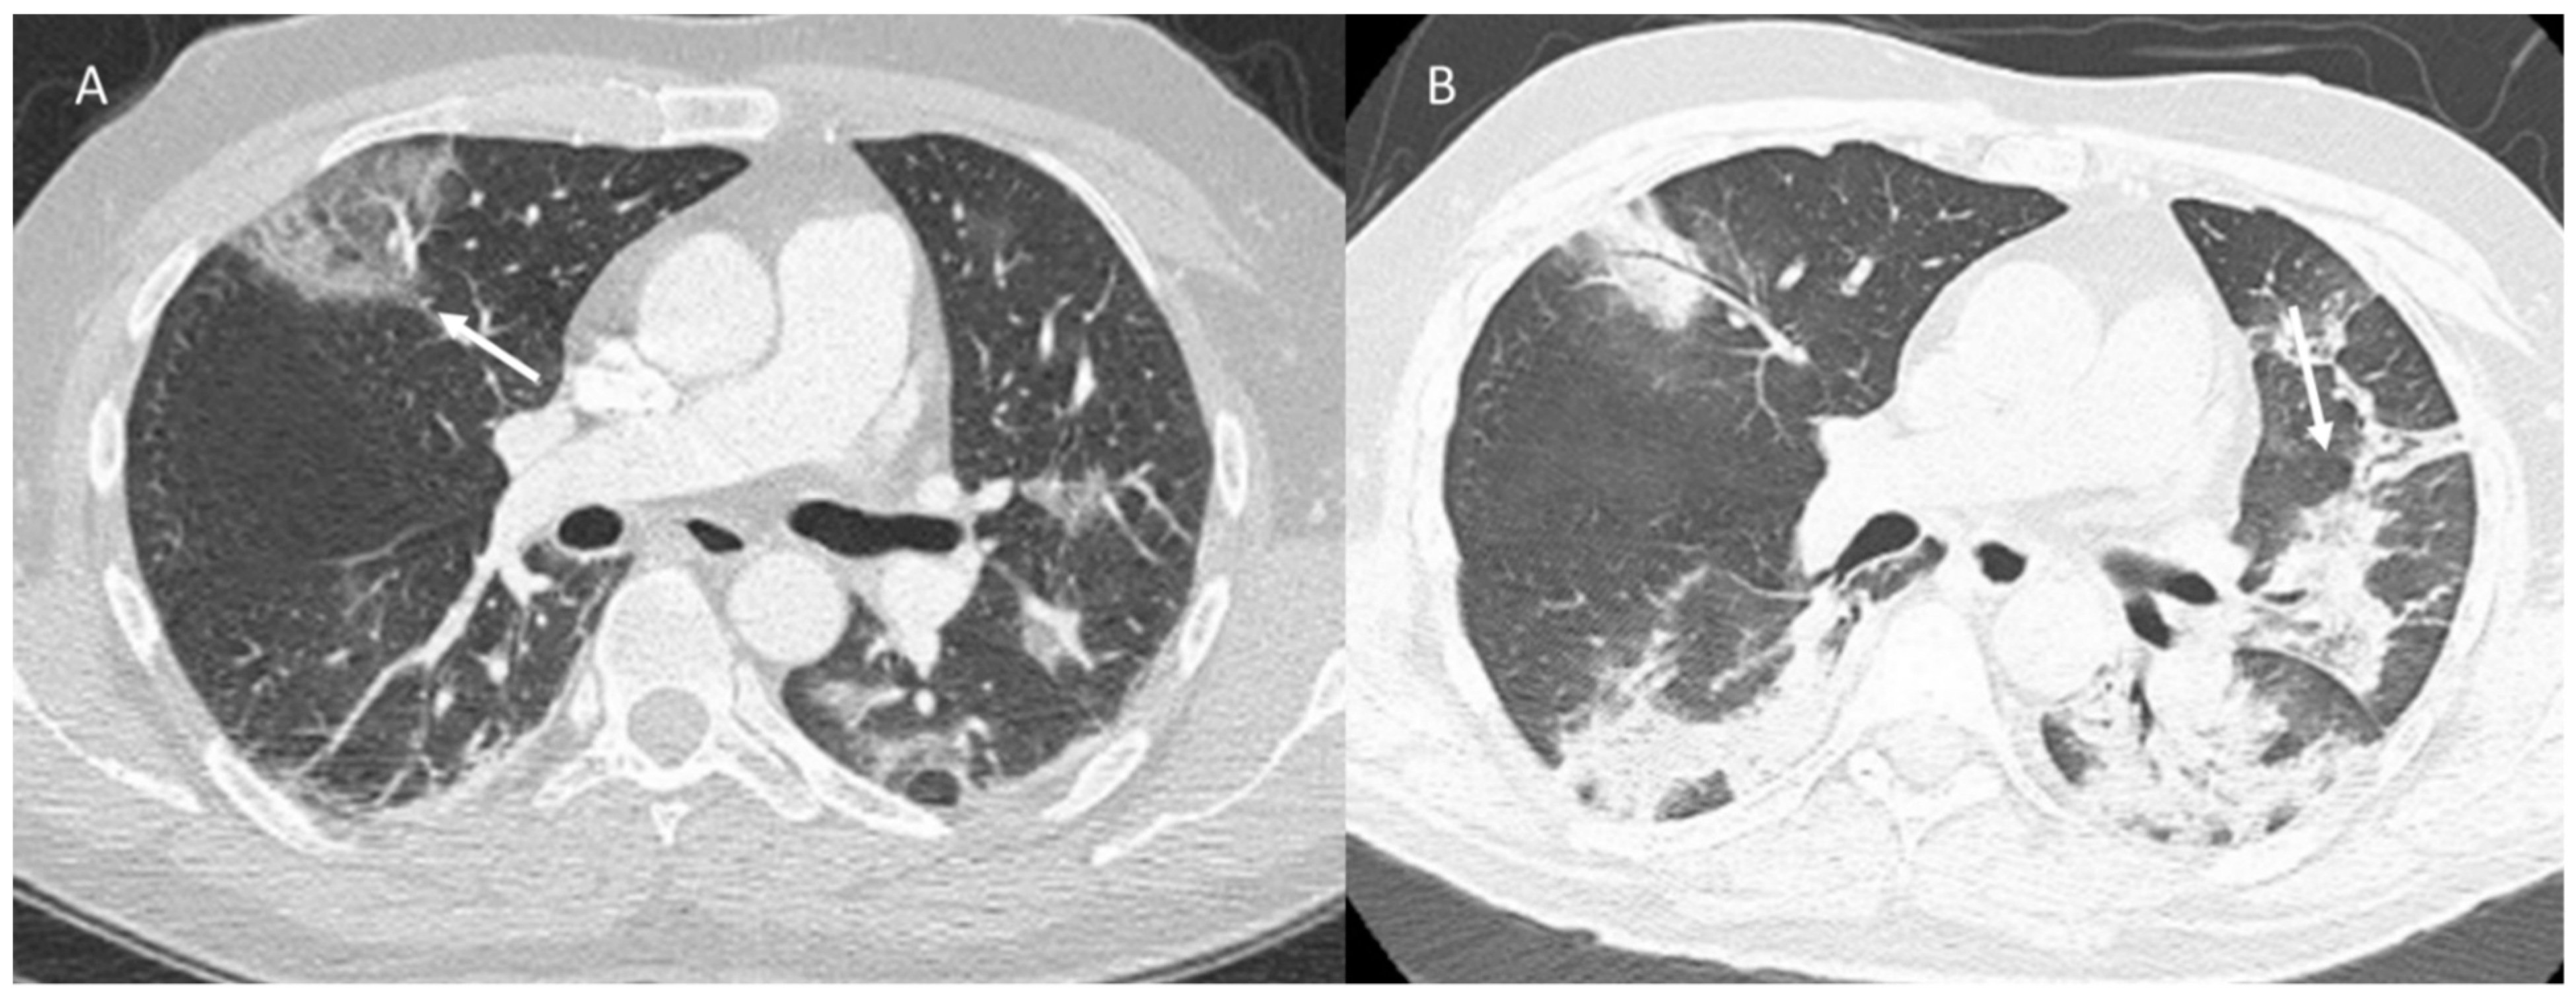

Immune checkpoint inhibitor (ICI)-related pneumonia could cause significant morbidity, with possible discontinuation of therapy and possible mortality [118]. The time to onset of pneumonia ranges from 9 days to over 19 months after the initiation of therapy, with a median time of 2.8 months [118]. Imaging plays a crucial role in this effect detection. Although X-ray may be an initial tool, CT is able to detect all subtle changes in pneumonitis and help to differentiate among subtypes, as described by Delaunay et al. [122]. Investigations described 64 cases of pneumonia with the following CT patterns: (a) organized pneumonia (OP) (23%), (b) hypersensitivity pneumonitis (HP) (16%), (c) non-specific interstitial pneumonia (NSIP) (8%) and (d) bronchiolitis (6%). Some patients were diagnosed with concomitant patterns and a distinctive pattern was not identified in 36% of cases [122]. OP’s pattern usually shows bilateral peribronchovascular and subpleural ground-glass and airspace opacities, with mid- to lower-lung predominance (Figure 2).

In addition, an inverted halo or atoll sign is detected. Pulmonary nodules, usually with peribroncovascular distribution and generally smaller (<10 mm) nodules, may also be detected. However, in some cases, the nodules may be nodular and massive with pointed edges, mimicking findings of malignancy [118,122]. These features should be distinguished from progression of malignancy (concurrent worsening of disease in other areas) and infection (clinical history, laboratory findings, response to appropriate therapy).

Acute interstitial pneumonia (AIP)–acute respiratory distress syndrome (ARDS) is not a model of ICI therapy-related pneumonia, although it is associated with a more severe clinical course and extensive pulmonary involvement with imaging. This pattern is characterized by geographic or diffuse ground-glass or consolidation opacities involving most, and sometimes all, of the lungs, although lobular sparing areas may be detected. There may also be a thickening of the interlobular septum and a “crazy pavement” pattern (Figure 3). The differential diagnosis is extensive and includes pulmonary oedema, haemorrhage, and infection. The findings of ARDS may also be due to extrapulmonary causes such as pancreatitis, sepsis and/or shock and transfusion reactions.

Figure 2. ICI-related pneumonitis. OP pattern on CT (axial: (A) and coronal: (B)): ground-glass and airspace opacities (arrows).

Figure 3. ICI-related pneumonitis. AIP-ARDS pattern on CT (axial: (A) and coronal: (B)): diffuse ground-glass opacities involving a majority of the lungs (arrows), although areas of lobular sparing can be detected.